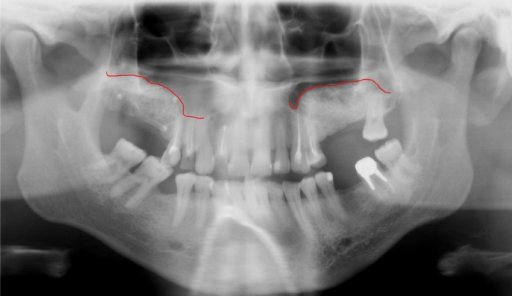

After

We prefer to work only with the patient's own bone tissue in accordance with the biological concept, which excludes the use of synthetic materials